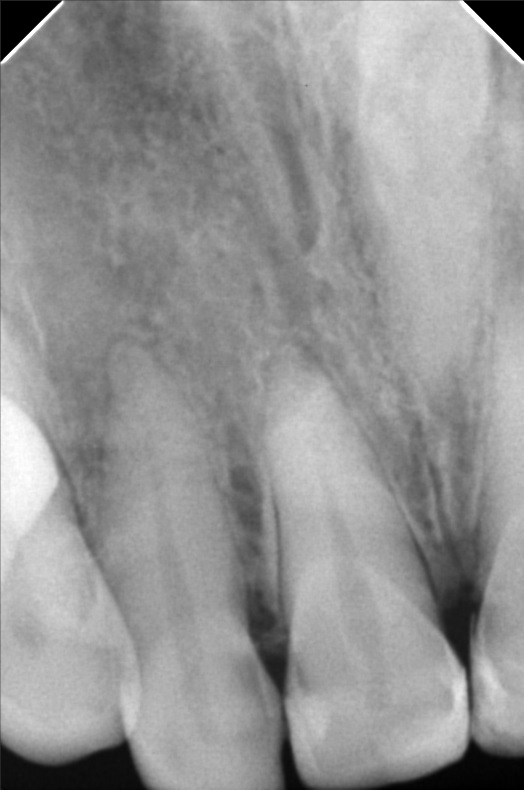

- 10/05/21 -0p/ Lc 11m/21M *22 subject for rct *11 distal repeat lc/ 21 repeat lc/ 12 lingual repeat lc 10/15/21- rct 22mm/ apical abcess laser done apexcal 10/22/21 - LC #12 mesial #11 Lc Distal #21 Distal LC #22 veneer #22 obturate- 22mm guttaflow 04/02/22- veneer due to spaces #41/42/43/31/32/ shade A3/ esthetica 08/25/2023- Cleaning veneer re-polish 11/12/22/21

- 22bonifacio101521.jpg